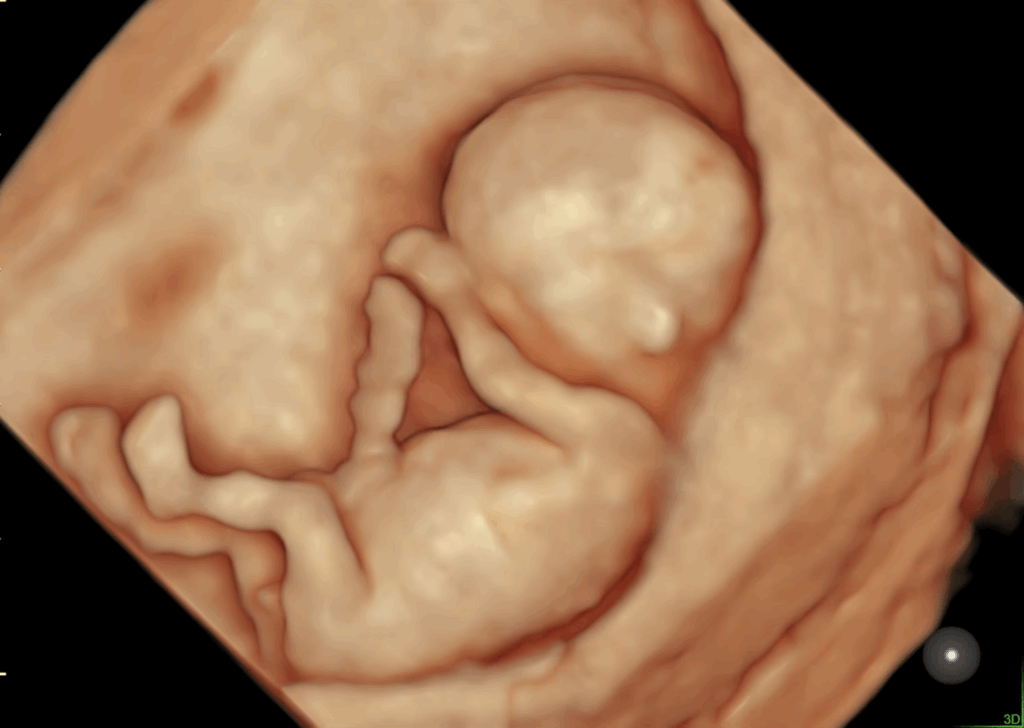

태아의 기본 구조와 형태

태아의 머리, 몸통, 팔다리 등

전반적인 구조가 임신 주수에 맞게 균형 있게 형성되고 있는지를 살펴봅니다.

한 장면이 아니라,

여러 각도에서 구조의 흐름을 종합적으로 확인합니다.